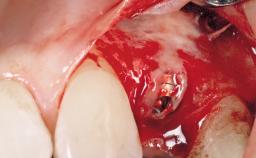

Immediate Placement of an Implant in a Maxillary Right Central Incisor Site

A 30-year-old female patient was referred to the office for the treatment of tooth 11. Her chief concern at the initial visit was to inquire, “Why is my tooth pink?” Upon clinical examination, it was determined that tooth 11 had a previous history of trauma and that the clinical crown had become noticeably pink in color as a result of internal resorption. This diagnosis was confirmed radiographically, indicating a large radiolucency involving the central and distal portions of the clinical crown. It was determined that restoration of this tooth was not possible, and that extraction was indicated. The presence of a mid-line diastema, which the patient wanted to reproduce, directed the treatment plan for tooth replacement utilizing a dental implant.

Bone Augmentation Horizontal|Simultaneous

Augmentation Materials Autogenous chips|Membrane

Placement Protocol Immediate implant placement

Socket Integrity Sufficient, with intact bone walls

Bone Volume Sufficient, with intact walls